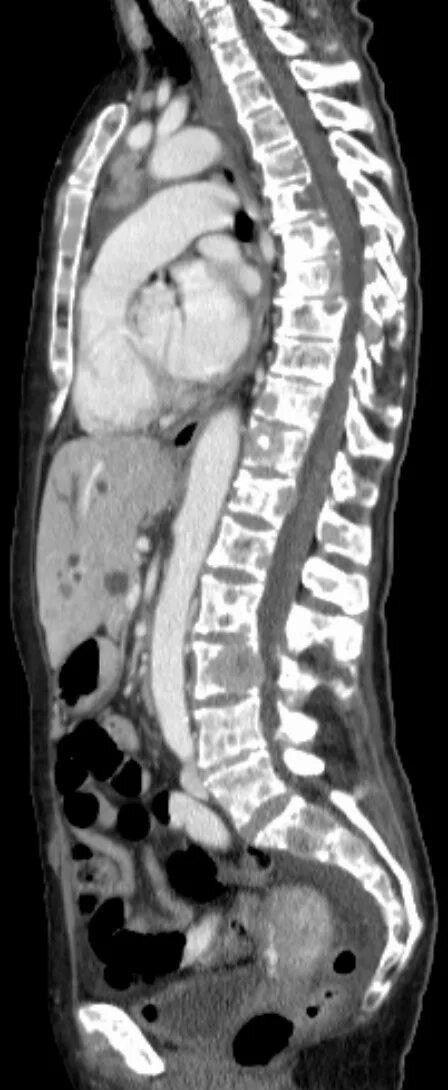

Метастазы в костном мозге